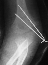

- TREATMENT: The patient was taken to the operating room where under

general anesthesia and tourniquet control the fracture was exposed utilizing

an anterolateral approach, taking care not to disturb the posterior vascular

pedicle of the lateral condyle. Following adequate reduction of the fracture,

2 diverging k-wires were placed across the fracture site.

The

patient was immobilized in a long arm cast at 90 degrees until radiographic

evidence of healing was apparent. The long arm cast and k-wires were removed

in clinic.